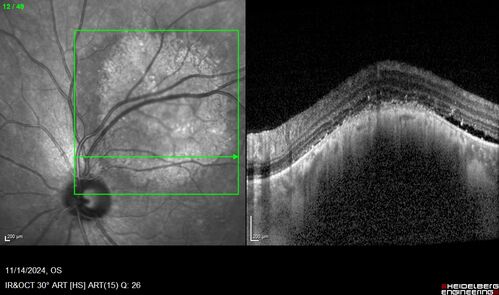

Small choroidal melanoma

28 year old man Serial images suggested that the lesion is growing

OD: sc20/16

OS: sc20/40+2

IOP: TP: OD:19 OS:16